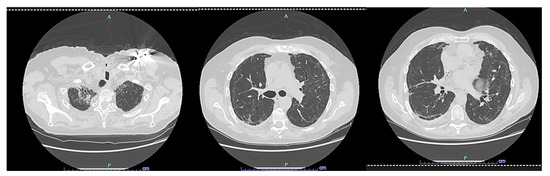

Significant Spontaneous Pneumomediastinum and Extensive Subcutaneous Emphysema in a COVID-19 Patient

2. Case Presentation